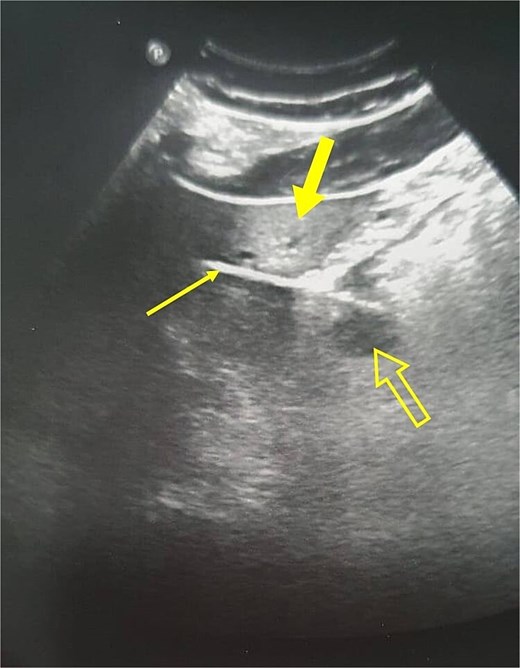

An abdominal ultrasound revealed a linear structure with posterior acoustic artifact and regional edema in the liver tissue, located between the distal stomach and the left liver lobe, suggesting the presence of a foreign body (Fig. 1). Additionally, the liver showed generalized fatty infiltration. The pancreas, spleen, and other abdominal structures were unremarkable, with no evidence of intra-abdominal free fluid.

Abdominal ultrasound showing a linear structure (thin arrow) suggestive of a foreign body, with posterior acoustic artifact and regional edema in the liver (thick arrow). The stomach is marked with a not-filled arrow.